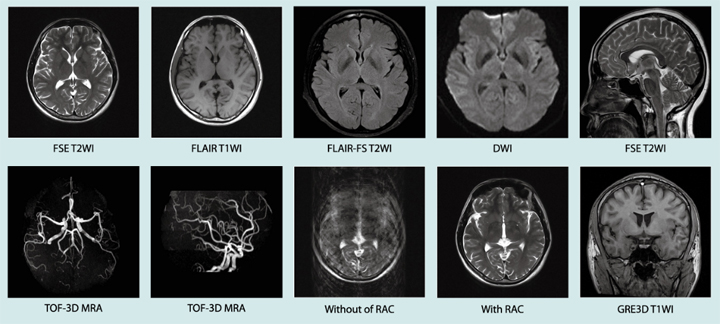

更优质的图像质量,快速、清晰

更丰富的成像功能,广泛、实用